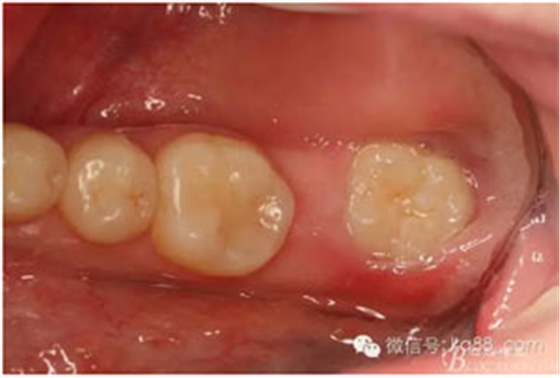

圖15.37拔除后的牙槽窩情況

圖16.清理牙槽窩、放膠原蛋白海綿

圖17.繼續(xù)填塞膠原蛋白海綿,充滿37牙槽窩。